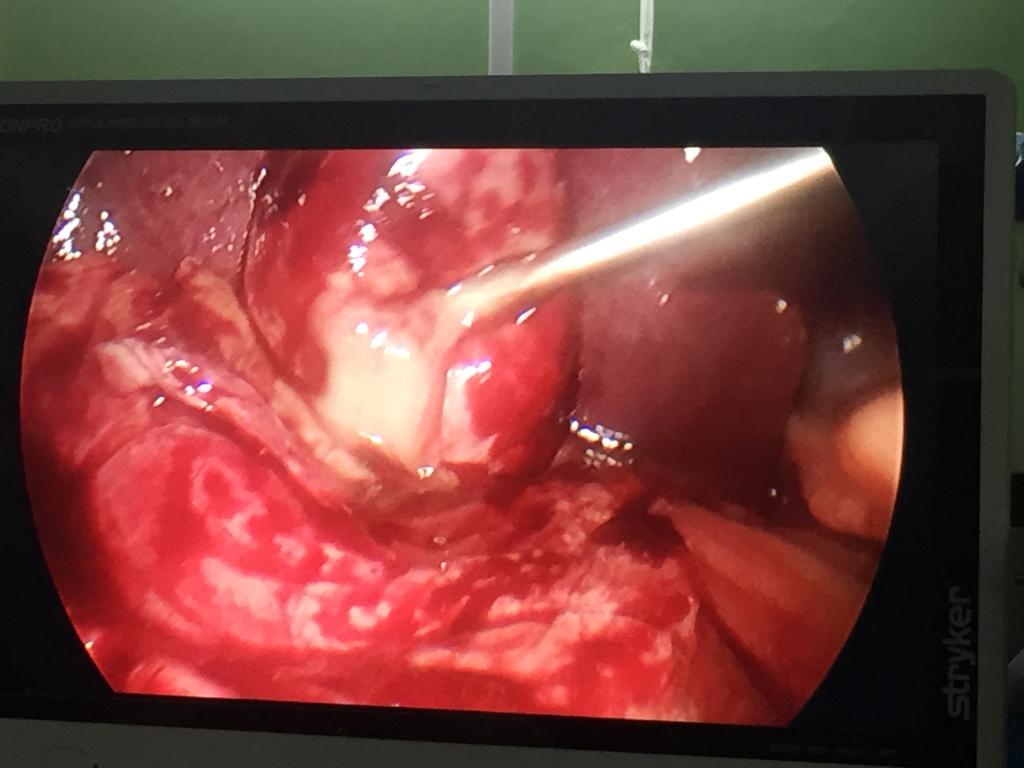

Difficult retrocecal appendix completely done laparoscopically

Difficult cases of appendicitis done completely laparoscopically